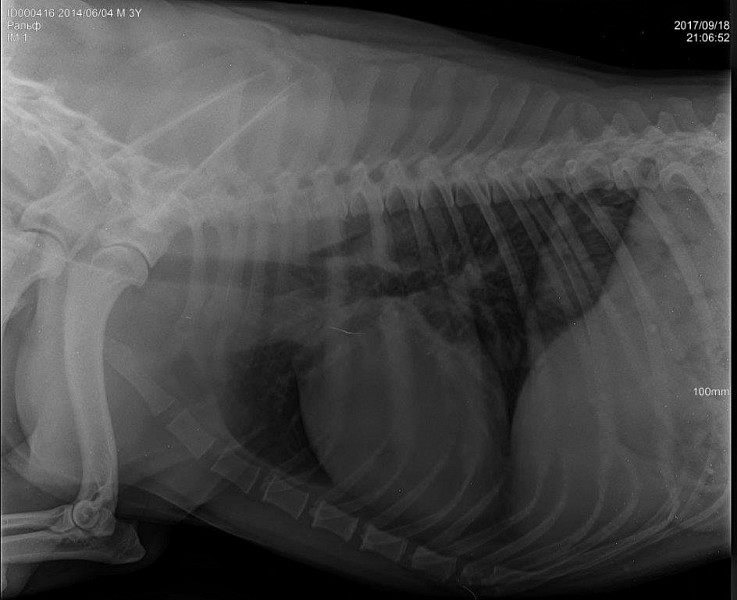

Рентгенодиагностика бронхопневмонии: Советы и примеры